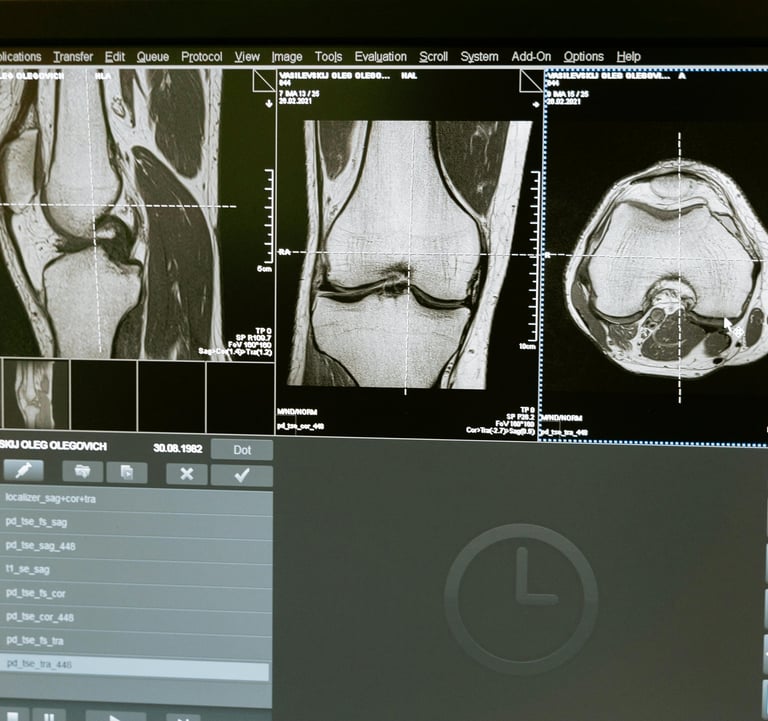

RADIOLOGÍA

Embárquese en este viaje educativo y conquiste el futuro de la radiología, donde el conocimiento avanzado se combina con la práctica , preparándolo para sobresalir en una carrera llena de oportunidades y logros.

El área de radiología, con docentes altamente calificados para brindarte lo mejor en esta nueva era de la inteligencia artificial y cómo cambia todo lo que sabemos del área, además de tener contenido de radiología, también habrá informática. x contenido de radiología para mantenernos actualizados en todo lo relacionado con PACS, HIS, LIS, RIS.